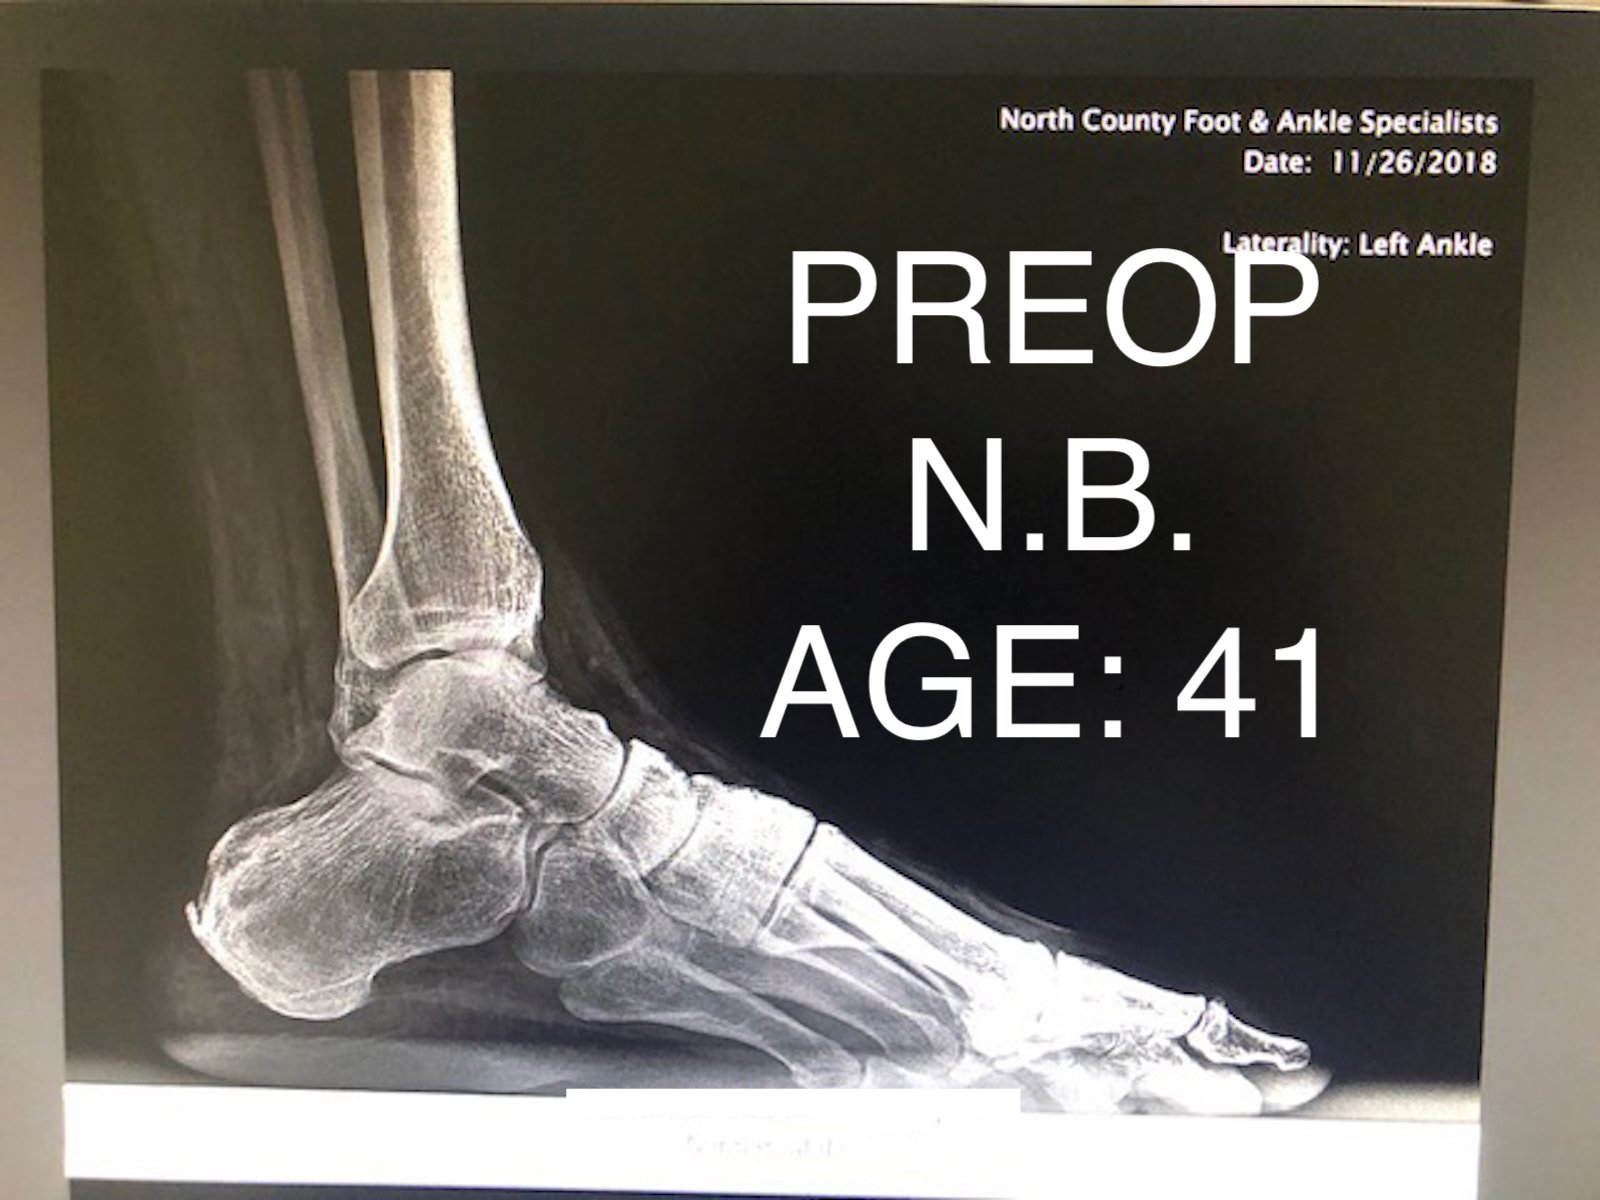

ANKLE FUSION